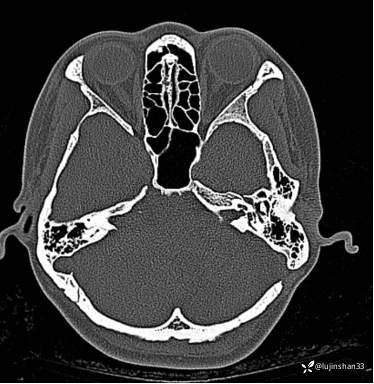

第二次术前CT及MRI